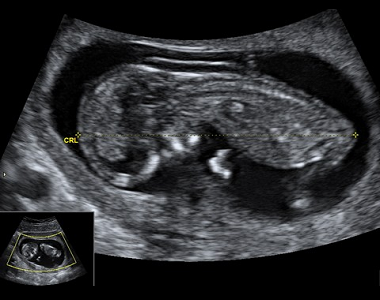

Zhruba nejpozději do konce prvního trimestru žena obdrží těhotenskou průkazku. Jedná se o nejdůležitější dokument v těhotenství, který by žena měla mít stále u sebe. Do schématu jednotlivých návštěv v těhotenské poradně, která mají v počátku interval 4-6 týdnů, jsou zahrnuta i tři ultrazvuková vyšetření. První v 11. až 13. týdnu těhotenství, sloužící k určení termínu porodu dle velikosti plodu, ale i vývojových vad plodu. Druhé ve 20. až 22. týdnu těhotenství, které je zaměřeno na velikost plodu, určení množství plodové vody, uložení placenty, pohybů plodu a také vývojových vad. Obdobně pak třetí ultrazvuk mezi 30. až 32. týdnem těhotenství.

Ultrazvuk

V průběhu těhotenství se provádí ultrazvuková vyšetření za účelem screeningu vývojových vad. Kdy jednotlivá vyšetření probíhají a co znamenají zkratky...

Prvotrimestrální screening

Prvotrimestrální screening je nejefektivnější metodou detekce vrozených vad v prvním trimestru. Kde by měl screening probíhat, z čeho se skládá a v ja...

Zkratky v těhotenské průkazce

Co je to cerkláž, glykosurie, cervix score, CRL, kolpo, cyto, oGTT, otevřené hrdlo, oligohydramnion? Jak se značí nadměrné množství plodové vody a co...